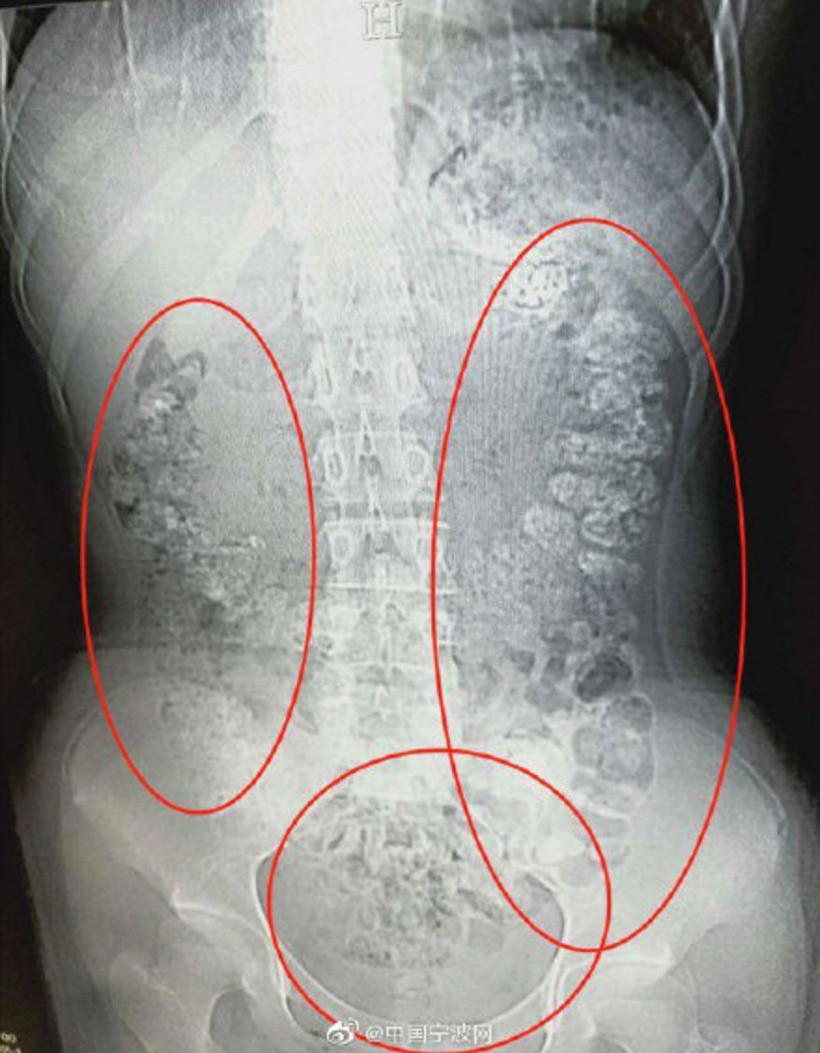

Xiao Shen isimli kız kabızlık şikayetiyle hastaneye kaldırıldı. Çekilen röntgende inanılmaz bir görüntüyle karşılaşıldı. Zira kızın mide ve bağırsaklarında jel kıvamında 100'den fazla yenilebilir top bulundu.

İlginç olay Çin'de yaşandı. Kabızlık şikayetiyle hastaneye kaldırılan küçük kızın midesinde 100 'Tapioca topu' denilen jelibon toplarının yapıştığı saptandı. Jelibon toplarının mideye yapışma sebebi ise doktorları bile şoke etti.

Daha sonra kızın en sevdiği içecek olan 'kabarcık çayı'ndan haddinden fazla tükettiği ortaya çıktı.

14 yaşındaki kıza tedavi uygulandı ve sindirim sistemini tıkayan toplardan kurtulması sağlandı.